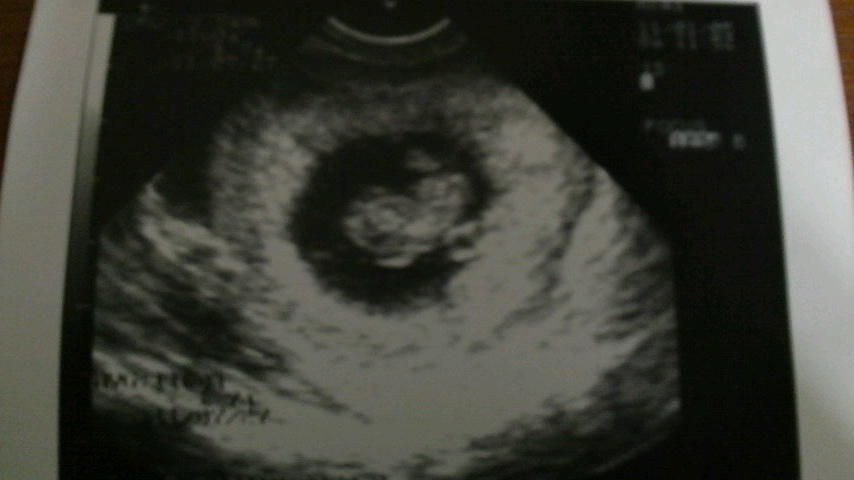

3人目ができました!!

現在妊娠8週目。

ちなみに予定日は2010年6月29日です。

かいりの誕生日は6月18日だから近いんだけど、かいりもちゅらも予定日よりも早く生まれてるんで、3番目も早くなってかいりと同じ誕生日になるかもね。